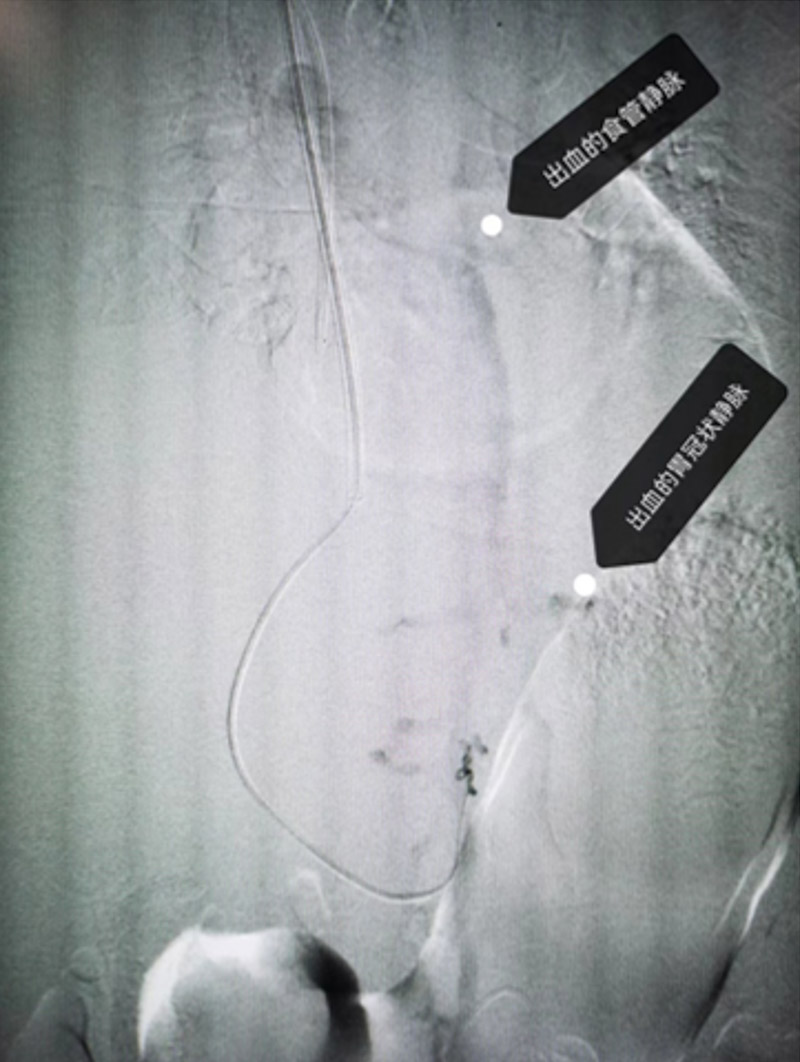

下一步的檢查證實(shí)了專家們的判斷,患者是食管靜脈重度曲張破裂出血,之所以出血量如此之大,根本原因還是肝硬化導(dǎo)致的嚴(yán)重門(mén)靜脈高壓。反復(fù)的藥物治療及內(nèi)鏡下止血解決不了根本問(wèn)題,復(fù)發(fā)出血幾率很高,建議患者接受TIPS手術(shù)。

所謂TIPS手術(shù),就是經(jīng)頸靜脈肝內(nèi)門(mén)靜脈-體靜脈分流術(shù),該手術(shù)可以將門(mén)靜脈血流經(jīng)支架分流到下腔靜脈,有效緩解門(mén)靜脈高壓,降低患者再次出血風(fēng)險(xiǎn)。

患者血素色持續(xù)下降,血管外科主任霍鑫迅速帶領(lǐng)介入團(tuán)隊(duì)開(kāi)展急診手術(shù),根據(jù)CT判定穿刺位置,從肝內(nèi)肝靜脈穿刺進(jìn)入門(mén)靜脈,利用DSA及彩超定位,在門(mén)靜脈跟肝靜脈之間放一個(gè)血管支架,建立一個(gè)新的分流通道——高壓的門(mén)靜脈血流直接經(jīng)支架分流道向下腔靜脈,2個(gè)半小時(shí)后,手術(shù)順利完成。患者的靜脈壓力從術(shù)中的38cmH2O(正常12-24cmH2O),降至術(shù)后的23cmH2O。